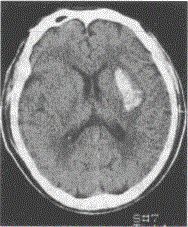

男,52岁。清晨锻炼时觉头痛,左侧肢体麻木和乏力,有高血压病史,半天后急诊。查体:嗜睡,右侧肢体肌力3级,腱反射高于左侧,右侧Babinski征阳性。脑CT见图示:

本题考查目的是综合临床资料和CT图像作出脑血管病的诊断。本病例为急性起病的脑血管疾病。脑血管病分为缺血性卒中和出血性卒中。脑血栓形成、短暂脑缺血发作、脑栓塞均为缺血性卒中范畴;高血压性脑出血为出血性卒中;根据缺血性卒中和出血性卒中的鉴别诊断表(见下表),可以得出B"高血压性脑出血"为正确答案。脑转移癌起病较慢,而且CT的病灶周围有大片水肿,为迷惑选项。